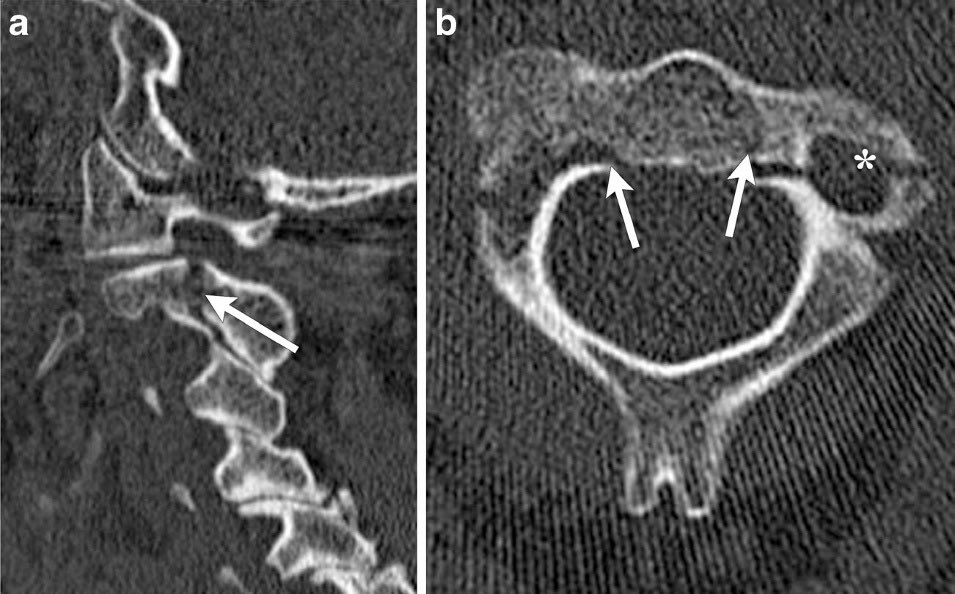

عشان نشرح الموضوع محتاجين نفهم شوية اناتومي اول ونعرف انه عندنا في المخ حاجة اسمها brain stem ودي بتطلع منها وبتجي مارة بيها كل الأوامر العصبية والأعصاب..الbrain stem بتنتهي بي حاجة اسمها medulla oblongata ودي بتمثل لينا بداية الحبل الشوكي في الراس وبتكمل في العمود الفقري لي تحت.

الفقرات زاتها بيهمنا نعرف فيهم ٢، الأولى او C1 وبيقولو ليها Atlas نسبة للشخصية اليونانية الكان اتعاقب بي إنه يشيل حمل العالم كله على أكتافه و C1 شايلة برضو حمل العالم بتاعتنا المتكون في الجمجمة على كتفها "المجازي".

تاني فقرة إسمها c2 ودي بقولو ليها axis لانها بتمثل لينا المحور البيسمح للرقبة انها تلف وتخلينا نقول لي زول لا بدون ما نفتح خشمنا..

المهم نرجع لي موضوعنا. في حالات الإعدام البيحصل انه لمن وزن الجسم كله يكون يقع على الفقرتين ديل بيقوم يتكسرو وغالبا الكسر بيكون في c2 ولمن تحصل الحاجة دي الc2 ممكن تضغط شديد على الmedulla oblongata المارة في نصها دي أو اذا الكسر بينتج عنه طرف حاد يخش في الmedulla يقطعو ويسبب وفاة

طيب في حاجة تانية مهمة جداً عايز انوه عنها.. انه في حالات الحوادث المرورية ولمن يتعرض الرأس لي ضربة من قدام بتخلي الرقبة يحصل ليها hyper extension لي ورا مثلا اذا قرب في قزاز ولا دركسون بدون حزام.. ممكن تسبب لينا نفس الكسر في c2..

لكن بما انه مافي حركة الزول ما بالضرورة يموت طوالي لانو ما حصل ضغط على الmedulla oblongata..

بيحصل الضغط متين؟؟ لمن نجي إحنا أولاد الفزعة أولاد الحلال نحرك المصاب بدون ما نثبت الرقبة.. ونجدعه في الطارة بي ورا وبتاع الطارة يطير بيهو وياكل اي حفرة "عشان يوصل بسرعة وينقذه"